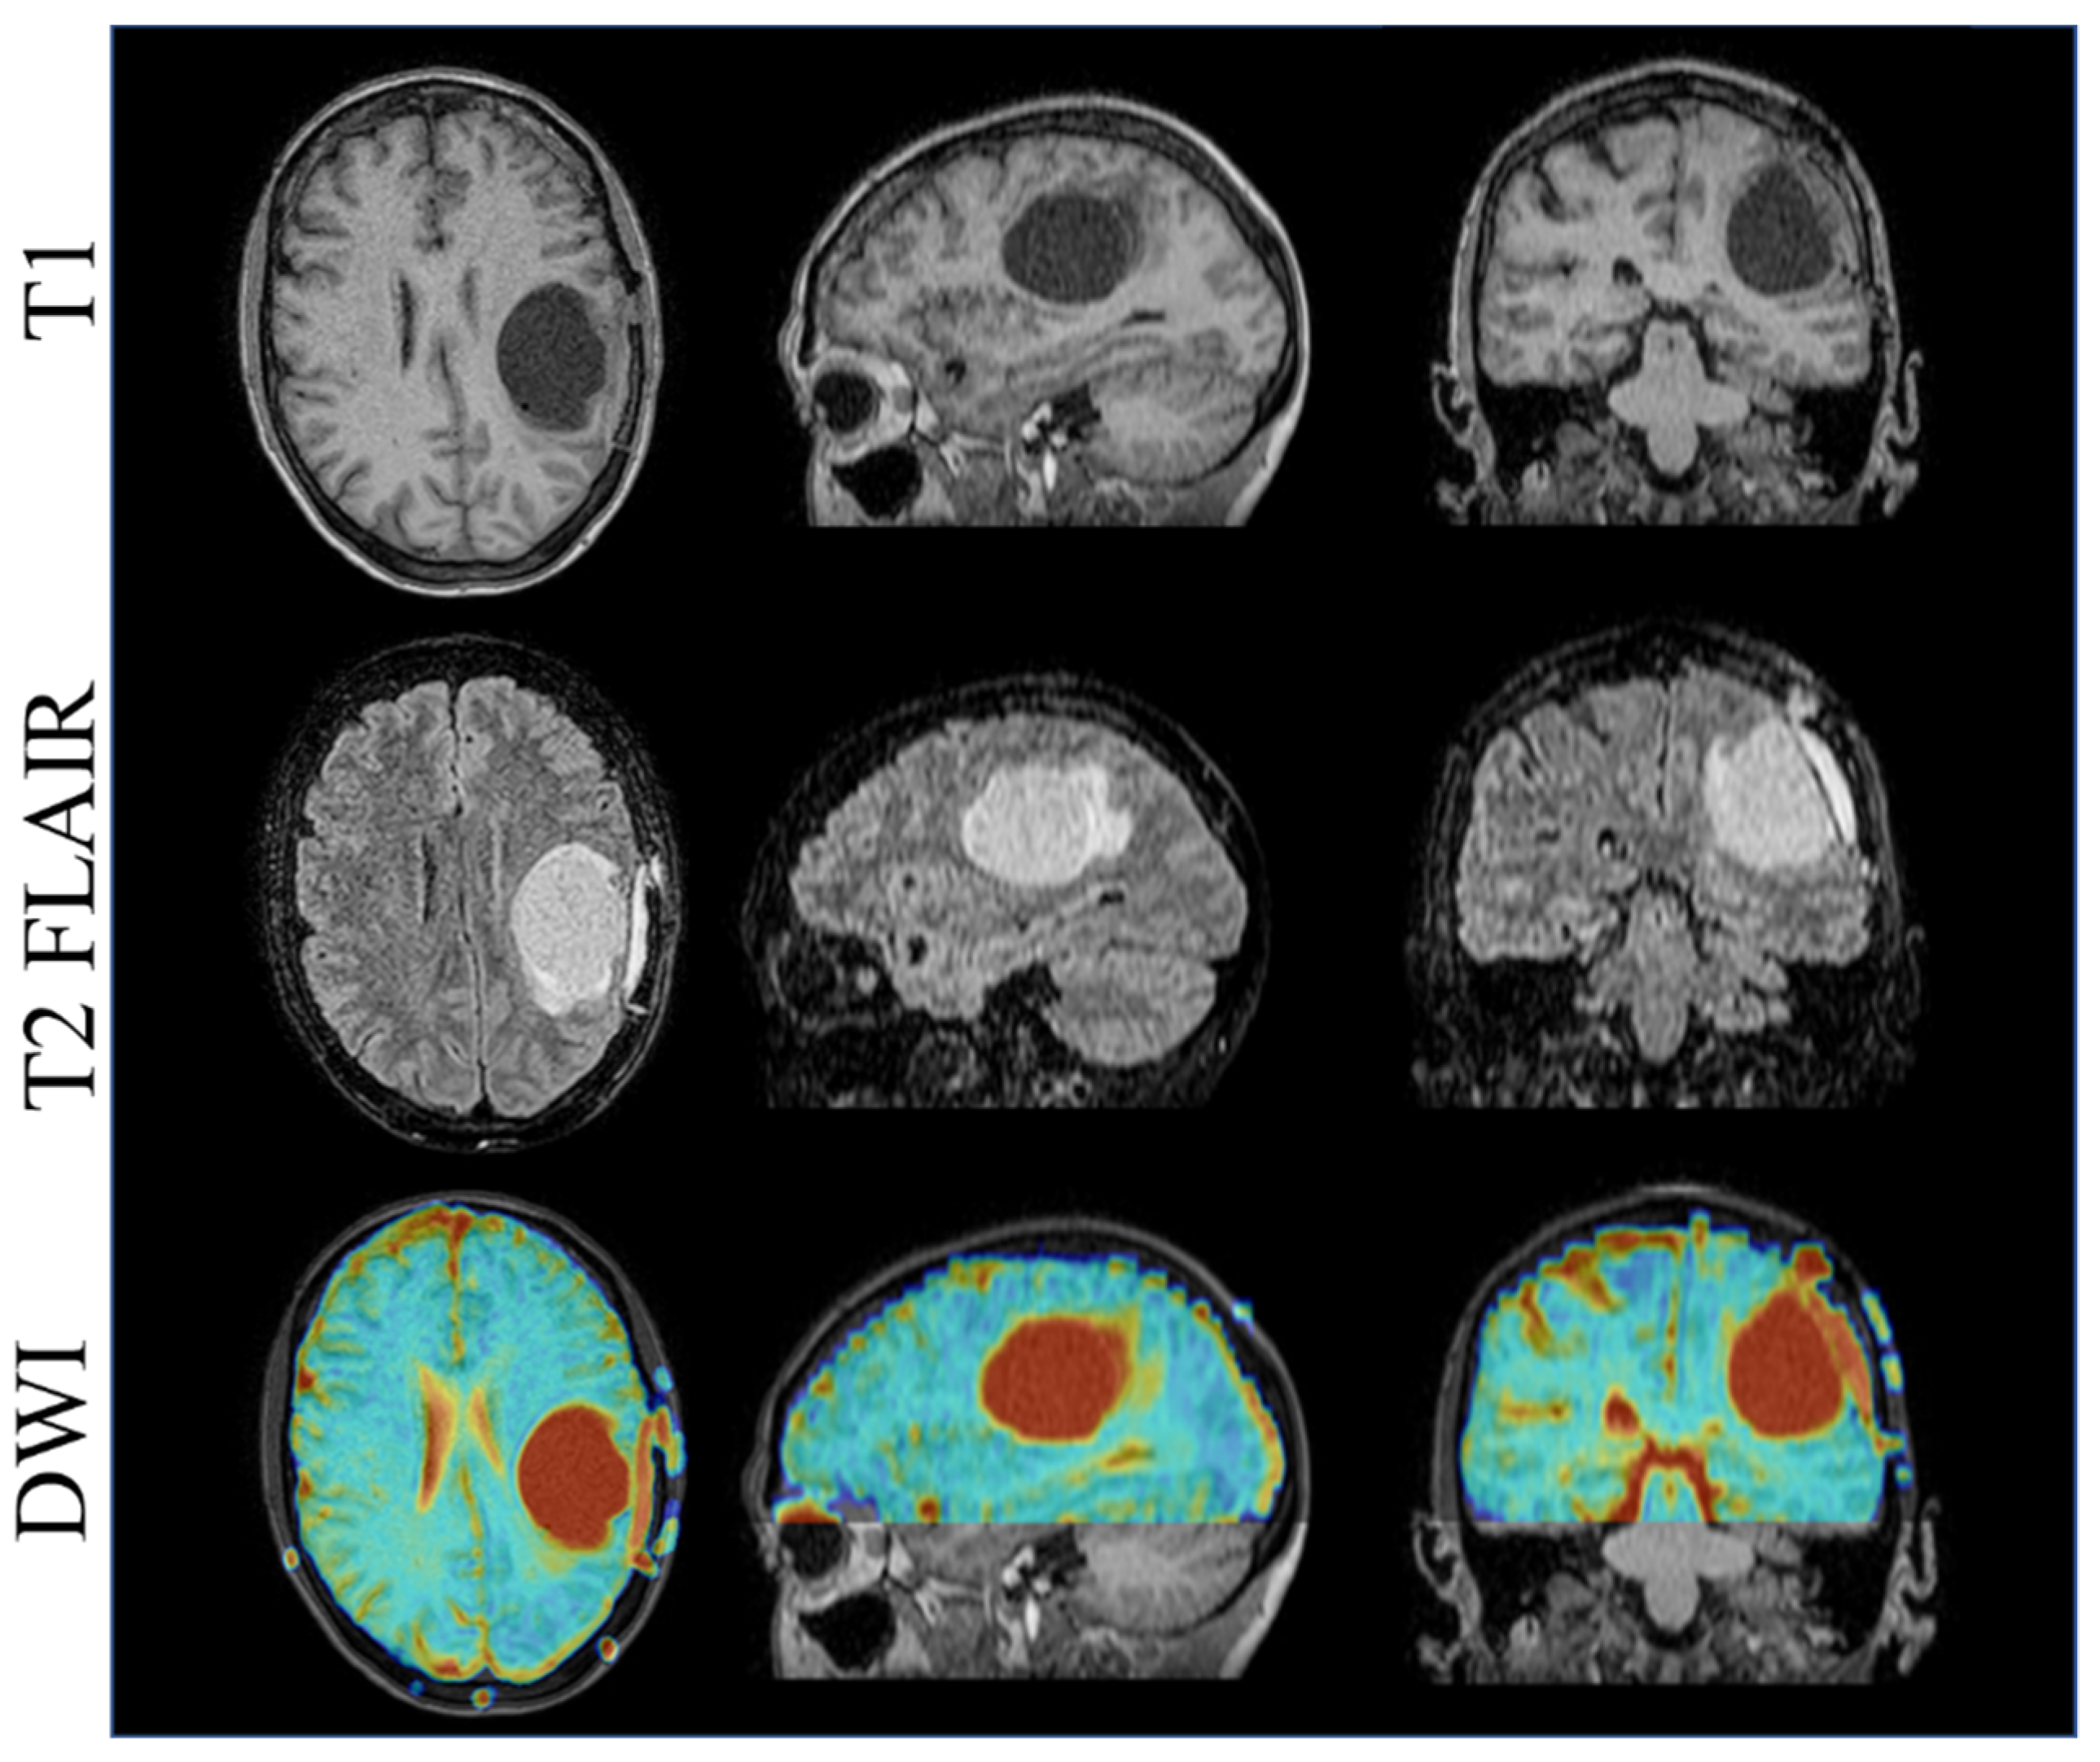

3.4. Brain